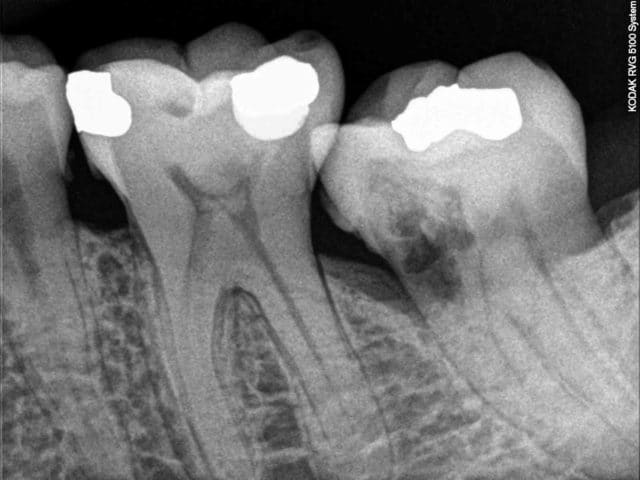

Aucune limites pour profiter de cette "merveilleuse nomenclature" !. Ici sensibilité au froid sur 15 +++, ne me voyant pas ouvrir un sachet de mta à 100 euros pour la gloire et gratos ca se termine en endo sc33 dans la foulée. Patient étudiant et sans doute arnaqué par la MNEF fera une éventuelle couronne plus tard, si ca pete !.-)))))

41 mn. dont 25 mn pour l'endo, 1mn pour le status et 15 mn pour le SC33.

Capture d e cran 2015 02 09 12.51 - Eugenol

Capture d e cran 2015 02 09 12.57 - Eugenol

Capture d e cran 2015 02 09 12.58 - Eugenol